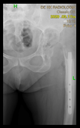

Figure 3.

The 3D-printed hemipelvis with the aiming device in the OR.

After approval, a label with a unique identifier was created on the 3D model, and then the aiming device was printed using a sterilizable, biocompatible, rigid, transparent photopolymer material (MED-610, Stratasys Ltd., Rehovot, Israel) [].